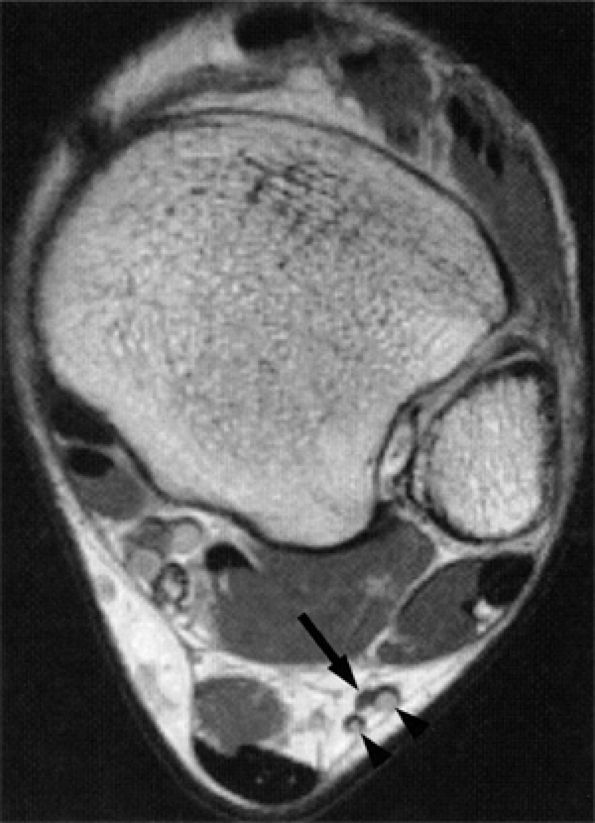

FIGURE 6.56 ● Neuropathy of the inferior calcaneal nerve (Baxter's neuropathy) in a 66-year-old patient with tarsal tunnel varicosities. Sagittal (A) and axial (B) T1-weighted images of the ankle demonstrate denervation atrophy of the abductor digiti quinti muscle (asterisk). (C and D). Normal abductor digiti quinti muscle (asterisk) in an asymptomatic patient for comparison.